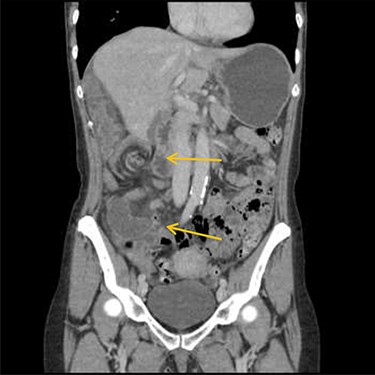

Patient initially diagnosed as biliary colic and surgical team had been contacted. Plain Abdominal radiograph showed dilated small bowels loops (Fig. 1). Chest radiograph revealed air under right hemi-diaphragm (Fig. 2). CT scan was done in emergency department and confirmed interposition of bowel between the diaphragm and the liver with a vascular/mesenteric pedicle swirl suggestive of malrotation or volvulus of the right colon. There was marked mural thickening and bold dilatation with high attenuation mucosa in keeping with closed loop obstruction and possible necrosis (Figs 3 and 4).

CT scan shows interposition of ileum, cecum and ascending colon between liver and diaphragm pushing right loop of the liver and gallbladder medially.

CT scan shows a vascular/mesenteric pedicle swirl suggestive of malrotation or volvulus with evidence of dilated closed loop obstruction.